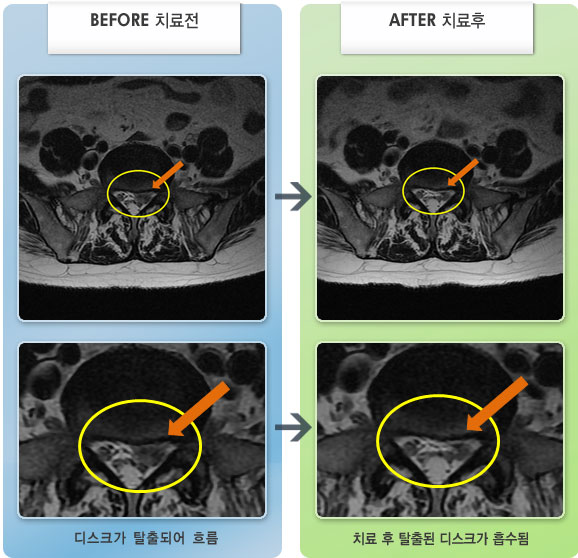

허리디스크

보라매 · 왕오호 원장

허리와 좌측 엉치 통증

촬영시기

2015.12.29 ~ 2018.10.11

2018.12.28